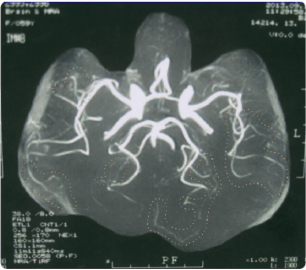

未病治療後(金澤点滴療法)

10日間の未病治療後には、脳の血管がはっきり見えるようになりました。 この時にはめまい・しびれが完全に改善され、もとの健康状態に戻ることができました。